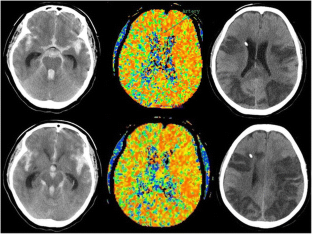

Disturbance of CT perfusion within 24 h after onset is associated with WFNS grade but not development of DCI in patients with aneurysmal SAH

Delayed cerebral ischemia (DCI) is a serious complication following aneurysmal SAH (aSAH) and remains a leading cause of morbidity and mortality. We investigated whether data from CT perfusion (CTP) within 24 h after onset are associated with DCI and its outcome.

We retrospectively examined plain CT, CTP, and CT angiography (CTA) of aSAH patients on arrival. We measured the average mean transit time (aMTT) and compared it with several clinical factors, such as the age, WFNS grade, Fisher group, delayed cerebral infarction, cerebral vasospasm, and modified Rankin scale (mRS), at 1 month. Regions of interest (ROIs) were quantitatively determined in cortical and two basal ganglia areas.

Delayed cerebral ischemia (DCI) developed in 11 patients and cerebral vasospasm in 28 patients out of a total of 86 aSAH patients scanned within 24 h after onset. The average MTT was correlated with the WFNS grade (p = 0.000), but not mRS (p = 0.128), age (p = 0.759), DCI (p = 0.669), or cerebral vasospasm (p = 0.306). On the other hand, DCI was associated with the Fisher group (p = 0.0056), mRS (p = 0.0052), and cerebral vasospasm (p = 0.000). Moreover, there were no significant differences in the average MTT within 24 h after onset between territories with and without DCI, or between patients with and without DCI.

The current findings suggest that disturbance of CT perfusion soon after the onset is associated with the WFNS grade but not with the development of DCI. Delayed cerebral ischemia may be solely caused by cerebral vasospasm due to a clot in the cistern, but not associated with early brain injury.